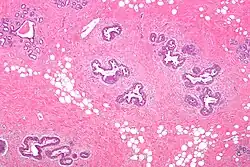

Histology

Early histological features expected to be seen on examination of gynecomastic tissue attained by fine-needle aspiration biopsy include the following: proliferation and lengthening of the ducts, an increase in connective tissue, an increase in inflammation, and swelling surrounding the ducts, and an increase in fibroblasts in the connective tissue.[26] Chronic gynecomastia may show different histological features such as increased connective tissue fibrosis, an increase in the number of ducts, less inflammation than in the acute stage of gynecomastia, increased subareolar fat, and hyalinization of the stroma.[24][26] When surgery is performed, the gland is routinely sent to the lab to confirm the presence of gynecomastia and to check for tumors under a microscope. The utility of pathologic examination of breast tissue removed from male adolescent gynecomastia patients has recently been questioned due to the rarity of breast cancer in this population.[57]